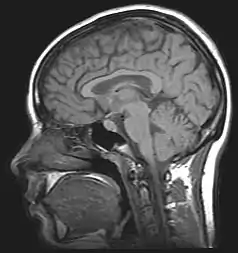

Alcohol-related brain damage alters both the structure and function of the brain as a result of the direct neurotoxic effects of alcohol intoxication or acute alcohol withdrawal. Increased alcohol intake is associated with damage to brain regions including the frontal lobe,[1] limbic system, and cerebellum,[2] with widespread cerebral atrophy, or brain shrinkage caused by neuron degeneration. This damage can be seen on neuroimaging scans.

Neuroimaging is used to study the effect that alcohol has on the brain. The two main imaging methods are hemo-dynamic and electromagnetic. These techniques have allowed for the study of the functional, biochemical, and anatomical changes of the brain due to prolonged alcohol abuse.[1] Neuroimaging provides valuable information in determining the risk an individual has for developing alcohol dependence and the efficacy of potential treatment.[1]

Magnetic resonance imaging (MRI) and functional magnetic resonance imaging (fMRI) are other commonly used tenichiques. These methods are noninvasive, and have no radioactive risk involved. The fMRI method records the metabolic changes in a particular brain structure or region during a mental task. To detect damage to white matter, the standard MRI is not sufficient. An MRI derivative technique known as diffusion tensor imaging (DTI) is used to determine the orientation and integrity of specific nerve pathways, allowing the detection of damage.[1] When imaging those with alcoholism, the DTI results show that heavy drinking disrupts the microstructure of nerve fibers.[1] Another MRI derivative technique, magnetic resonance spectroscopy imaging (MRSI), can provide further information about the brain's neurochemistry and can detect the distribution of certain metabolites, neurotransmitters, and alcohol.